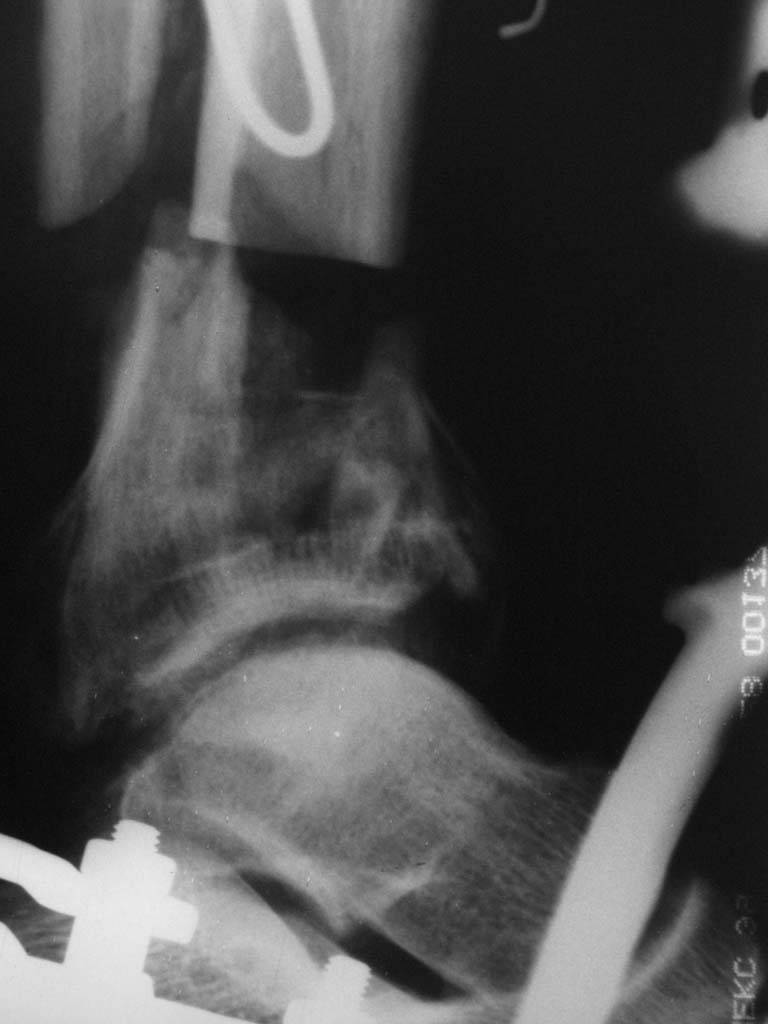

В случае гладкого заживления раны, при условии положительного решения вопроса с металлом, планируем перемонтаж аппарата Илизарова, дополнительную резекцию дистального отломка, выведение полокости голеностопного сустава в правильное положение (см. боковую Р-грамму), одномоментно остеотомия большеберцовой кости. После восстановления длинны голени, по всей видимости,  артродез голеностопного сустава.

Рентгенограммы прилагаются. Фото местного статуса выложу в ближайшее время.

Имя     : боковая.jpg